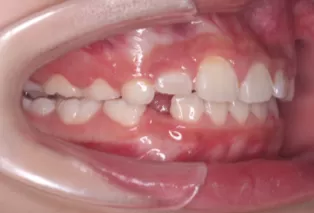

Intraoral photos